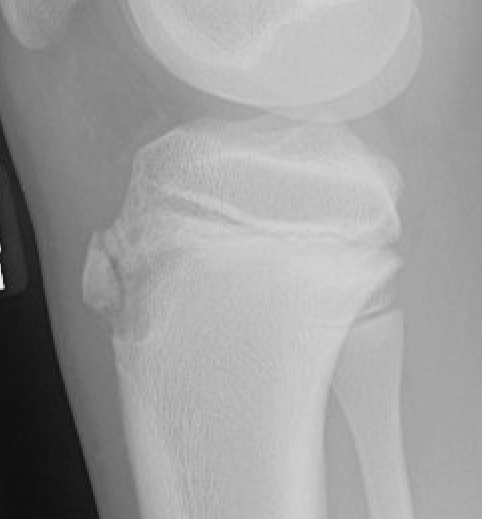

Type IB

Type IIB

Type III

Comminuted Type III